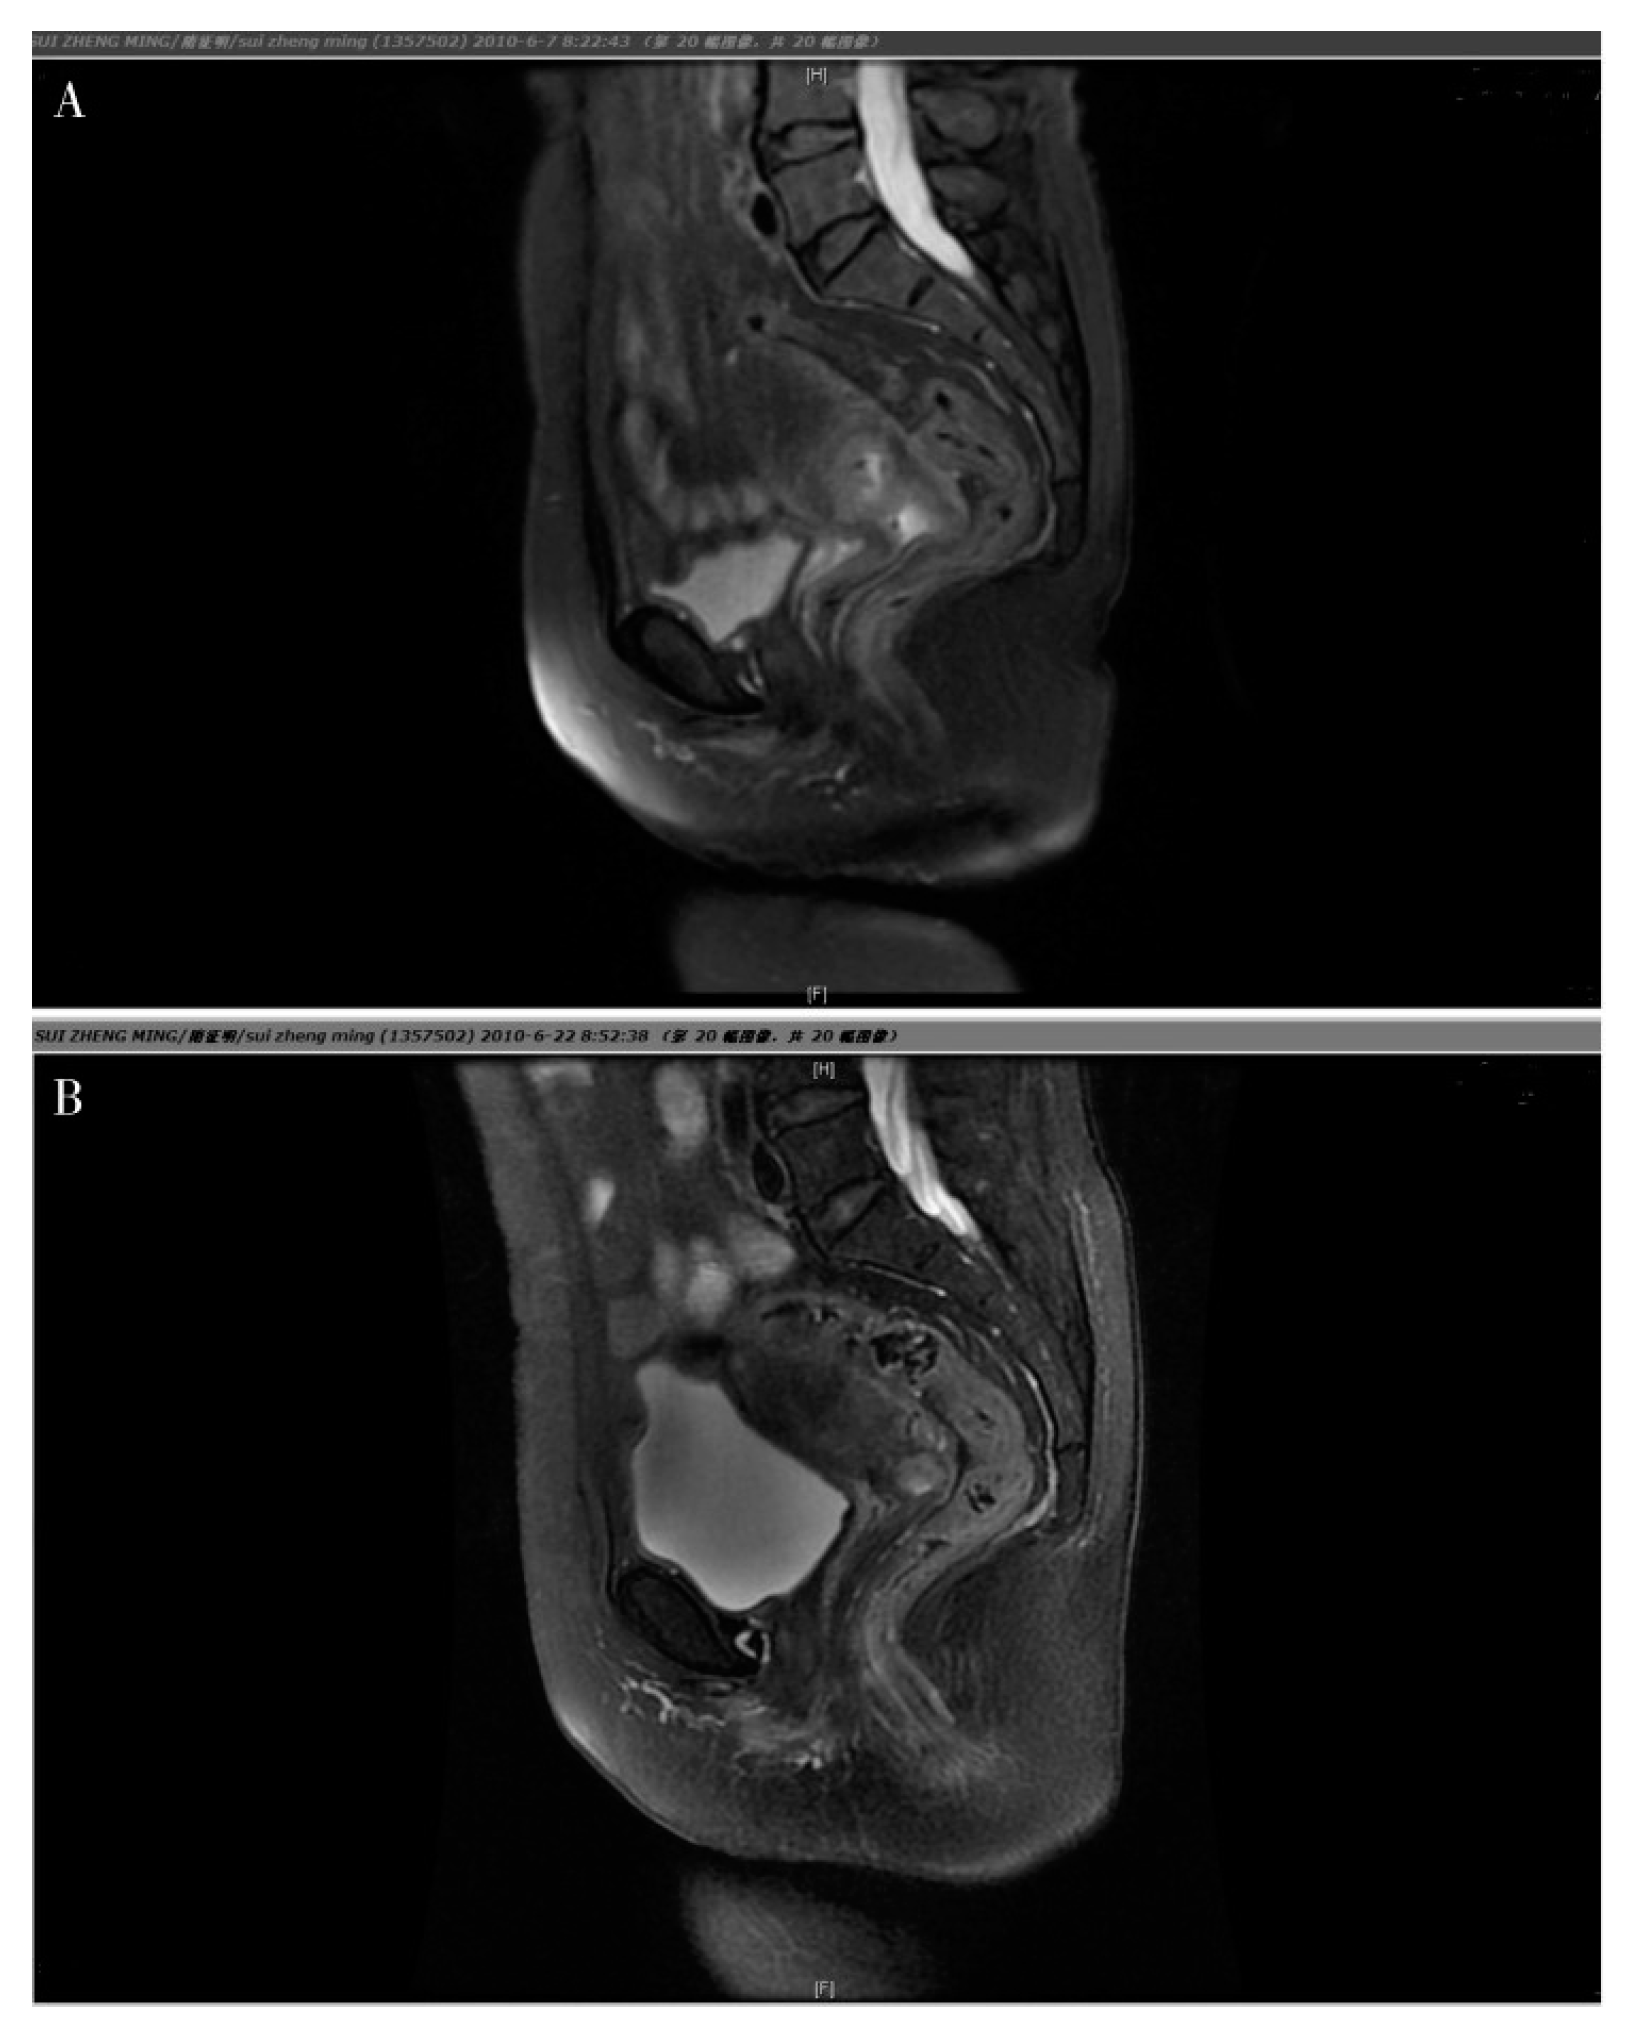

Figure 1. Magnetic Resonance Imaging (MRI) for a cervical carcinoma, objective response of NACT. A. Prior to chemotherapy, the tumor was large and it was difficult to distinguish it from the surrounding tissues. B. following NACT, the cervix returned to it’s natural shape and the tumor reduced considerably.